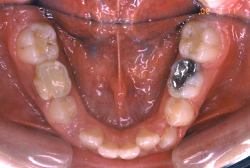

「左奥歯でものが噛めない」という主訴で来院したケースです。診断の結果、基本的には「叢生」という隙間が足りないと言うことが原因の凸凹症例でしたが、左下の乳歯が高校生になってもまだ残存している状態で、そのせいで噛み合わせが極端に悪くなっていました。

検査の結果、乳歯の下には後継ぎの永久歯が先天的に欠如していました。配列の凸凹が厳しく非抜歯で矯正することは難しく、仮に無理をして非抜歯治療をしても後々「後戻り」が懸念されることから、このような症例の場合は通常、上下顎左右第一小臼歯を抜歯させていただくのですが、左下は乳歯を抜歯して、第一小臼歯は残すことにしました。これで結果として、小臼歯部を上下左右で一つずつ減らしたのと同じ状況になります。治療後は歯並びが綺麗になっただけでなく、噛み合わせ的にも正しい状態が確立しています。

このように、先天的に永久歯が足りないという症例は最近増えています。親知らずはなくても特に問題になりませんが、その他の歯が足りないと言うのは審美的にも機能的にも重大な障害となります。しかし、矯正治療を正しく行えば、結果として歯がすべてあった場合と全く同じ仕上げにすることも可能です。